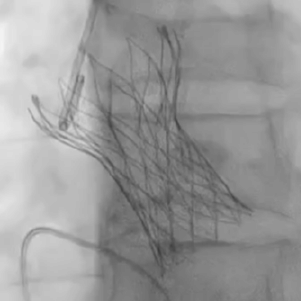

从三叶瓣重度钙化到二叶瓣畸形的根部解剖,从单纯主动脉瓣反流到入路极端迂曲挑战的案例。TaurusOne凭借其优异的柔顺性,支撑力强及内外层双侧裙边的特点,都能从容应对复杂的临床患者解剖结构。从患者的临床选择到术后的长久获益,从手术入路的种类到术中操作的注意事项,从围术期卒中的循证医学到术后的抗凝抗栓用药规范,在线专家共同交流彼此中心的围术期TAVR经验和分享现阶段经导管主动脉瓣置换的诊疗策略。针对当前TAVR领域多个热点学术问题进行了热烈的讨论,现场可谓精彩纷呈、高潮迭起。专家们纷纷借此契机相互交流探讨,分享各自的单中心经验,力求进一步提升TAVR手术的安全性和有效性,为主动脉瓣相关疾病的患者带来长远综合获益。